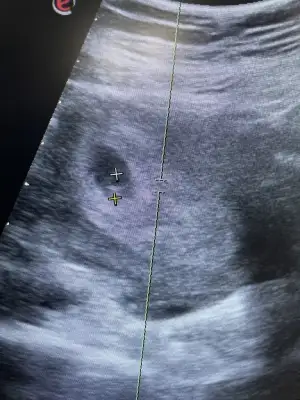

Kızlar merhaba sat a göre 6+1 bugün 2 gün önce kesemizi görmüştük ve muayenenin akşamında 1 damla toz pembe kahve karışımı akıntım oldu, ertesi gün yine 1 damla aynı şekilde bugünde 2 damla geldi ağrım yok böyle bişey yaşayan var mı 😞 ilk gebeliğimde kahverengi akıntım vardı progestana rağmen geçmemişti ve kaybettim.

Doktorumla konuştum önemli bişey olduğunu sanmıyorum Protestan kullan dedi dayanamadım devlete gittim kesemi gördüm 10 mm olmuş şükür lekelenmenin de normal olduğunu söyledi bu haftalarda 🙏